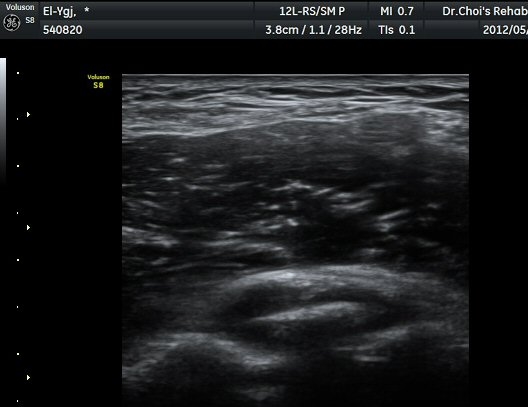

ÆÈ²ÞÄ¡ ³»Ãø Á¾´Ü¸é°ú Ⱦ´Ü¸é°Ë»ç¿¡¼­ ȰÂ÷ ¾Õ°ú °¥°í¸®µ¹±â¿Í(coronoid fossa)¿¡ ¼ö¾×Àú·ù°¡

°üÂûµÇ°í °¥°í¸®µ¹±â¿Í¿¡ °í¿¡ÄÚ »À µ¢¾î¸®°¡ °üÂûµÈ´Ù(±×¸² 2, 3).